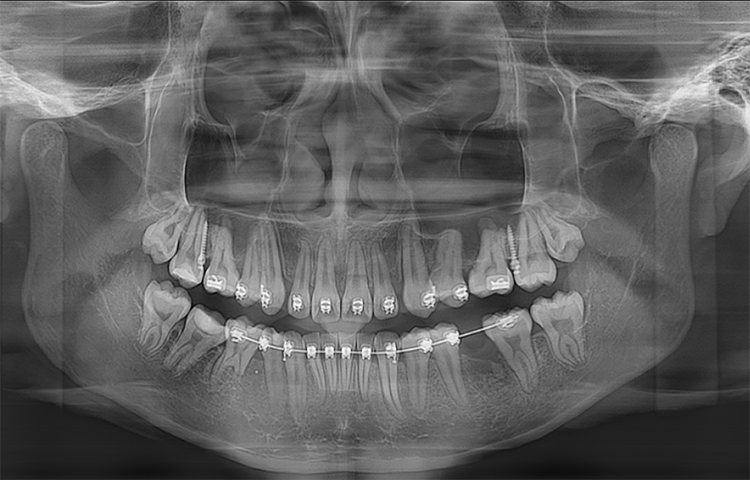

Панорамный аппарат Meyer обеспечивает стоматологов высококачественными панорамными и цефалометрическими снимками, который может быть использован для диагностики всего зубного ряда, нижней челюсти и ВНЧС. Он также подходит для оценки челюстно-лицевых переломов и разработки планов ортодонтического лечения.

Скриншоты снимков